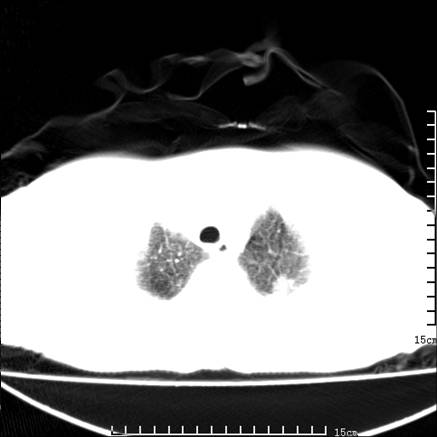

女,王某,58岁,咳嗽三个月余,基层医院二个月前诊为肺结核,用抗结核药二个月无明显疗效。

心包积液致肺瘀血.右侧周围型肺癌伴肺内转移,中间裂积液,叶间胸膜肥厚.右上肺大泡,右侧胸膜肥厚.

双肺继发型tb,心功能不全并肺淤血、心包、双侧叶间裂积液,肺大泡,右下胸膜肥厚钙化。

支持  双肺继发型tb,心功能不全并肺淤血、心包、双侧叶间裂积液,肺大泡,右下胸膜肥厚钙化。